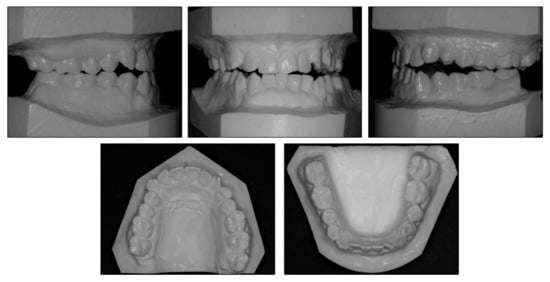

2.1. Diagnosis and Etiology